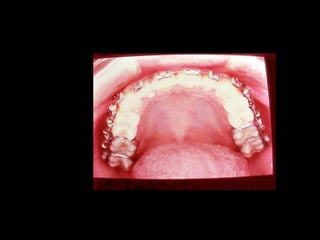

Modelos PreoperatoriosModelos Preoperatorios

Arcada Superior:

Forma oval

Paladar profundo

Totalidad de órganos dentarios a excepción de tercer molar izq.

Restauraciones deficientes

Arcada Inferior:

Forma ovalada

Colapso posterior

Ligero apiñamiento de anteriores

Rotación de premolares

Arcada Superior: Forma oval Paladarprofundo Totalidad de órganos dentarios a excepción de tercer molar izq. Restauraciones deficientes Arcada Superior: Forma oval Paladar profundo Totalidad de órganos dentarios a excepción de tercer molar izq. Restauraciones deficientes Frente: Línea media desviada Mordida cruzada anterior Frente: Línea media desviada Mordida cruzada anterior Arcada Inferior: Forma ovalada Colapso posterior Ligero apiñamiento de anteriores Rotación de premolares Arcada Inferior: Forma ovalada Colapso posterior Ligero apiñamiento de anteriores Rotación de premolares